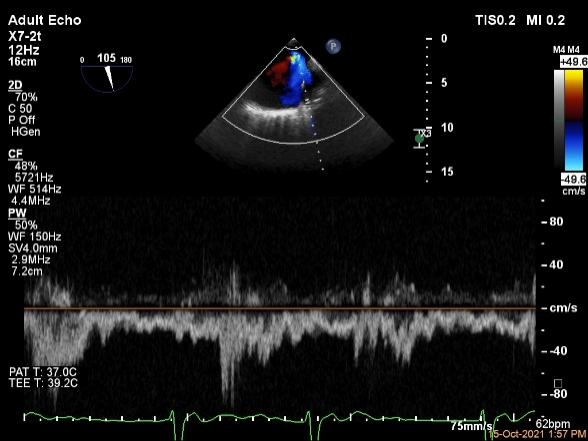

肺静脉血流频谱恢复正向